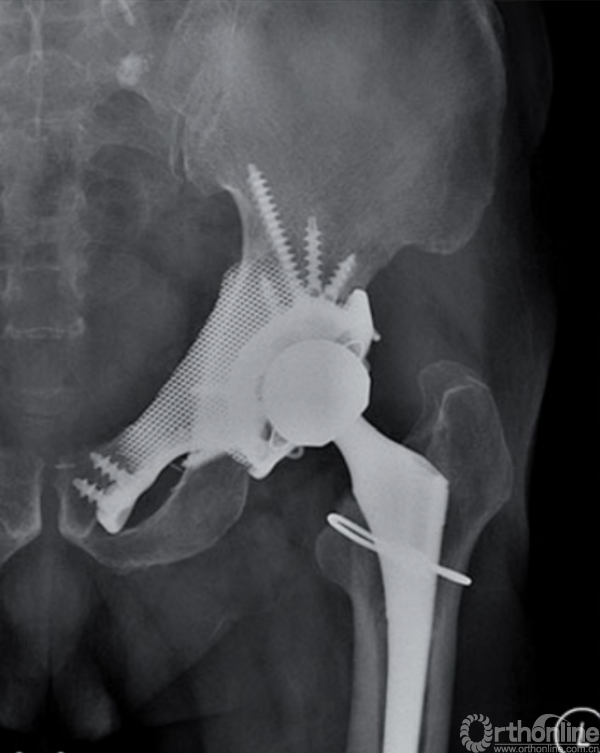

马鞍式假体未与宿主骨形成稳定的骨性连接,整体功能较差,并且并发症发生率较高[2-5](图1)。冰激凌假体与宿主骨的连接更加紧密,但不适合骨盆I区大部分切除的骨缺损,不能重建完整骨盆环[6-10](图2)。组配式半骨盆假体组装灵活,且可进行骨盆环完整重建,但其安装技术要求高,假体组件间存在断裂风险,不匹配得假体与宿主骨锚定将直接影响骨整合,最终易导致松动[1,11-15](图3)。

图3 组配式半骨盆假体